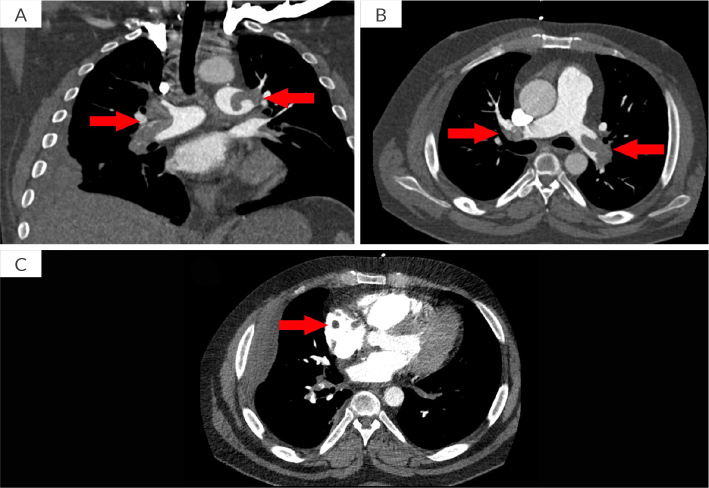

Case description: A 37-year-old male with untreated rheumatoid arthritis presented to the emergency department with dyspnea and chest pain, ultimately found to have massive bilateral PE with CIT. This was successfully treated with percutaneous thrombectomy using the INARI FlowTriever device (Inari Medical, USA).

Discussion: This case is accompanied by uncommon post-thrombectomy imaging that vividly demonstrates the thrombus burden in the majority of bilateral pulmonary vessels, providing valuable visual insight into the disease process and intervention efficacy. Rheumatoid arthritis is an independent risk factor for PE, deep vein thrombosis, and venous thromboembolism, highlighting the importance of treatment.